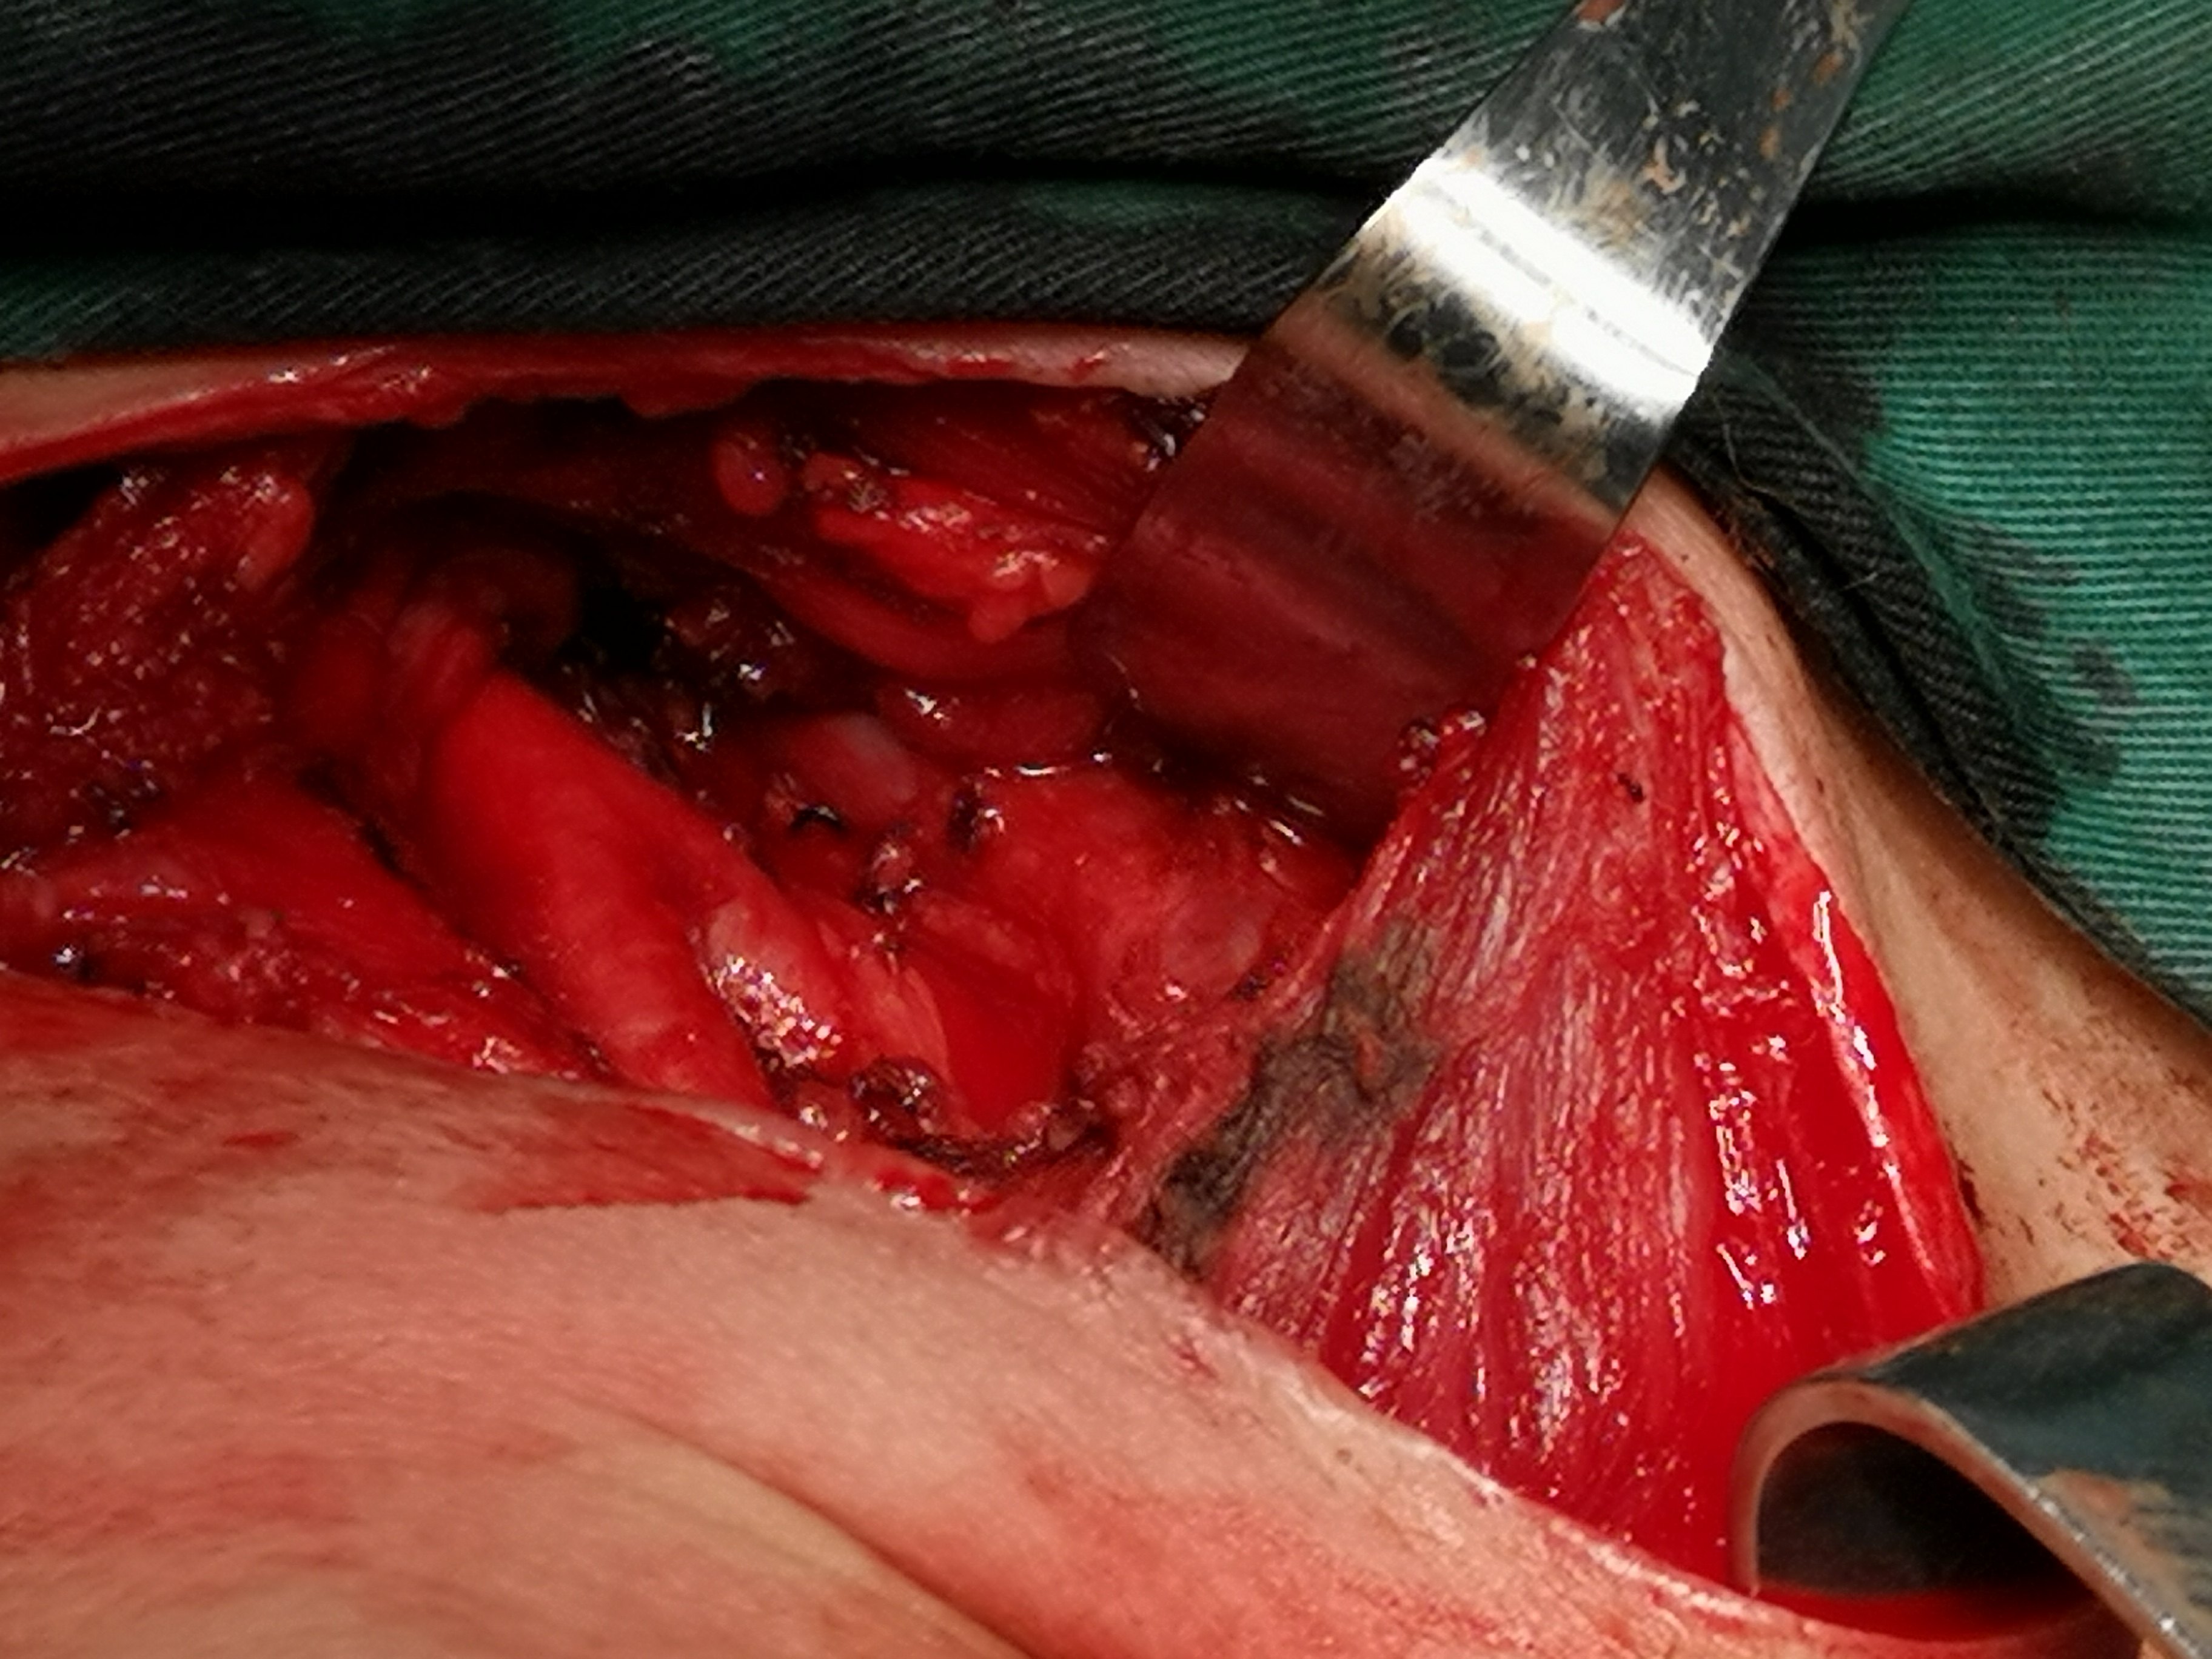

甲状腺癌再次手术

病例2 右2,右4R区,左6区残留,颈部切口清扫,未开胸